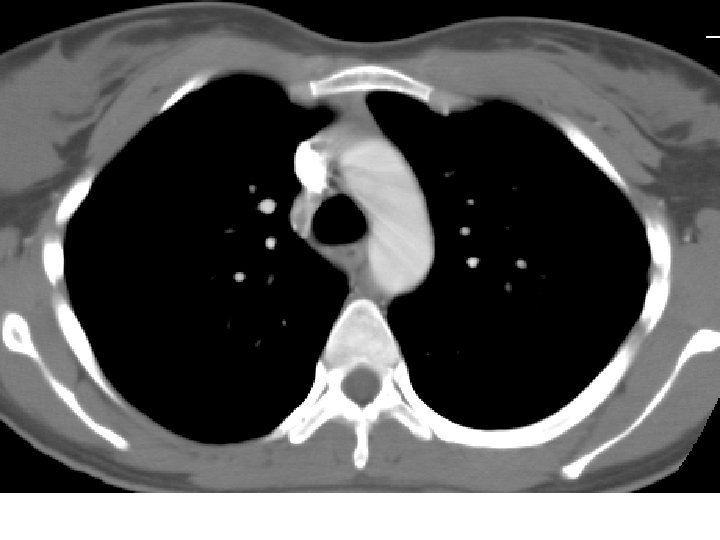

Bronchopulmonary Sequestration Definition • Non-functioning lung tissue • Separated from normal bronchial tree • Vascularized by a systemic artery Two Forms • Intralobar (ILS): within the visceral pleura • Extralobar (ELS): separated from the lung by its own pleura

Intralobar Pulmonary Sequestration (ILS) Characteristics • More common type • May present at any age • Generally as recurrent infection • No sexual predominance • Almost exclusively affects lower lobe • Arterial supply: descending aorta • Venous drainage: pulmonary veins

Pulmonary Sequestration Complications • Recurrent infection • Heart failure • Intralobar malignancy